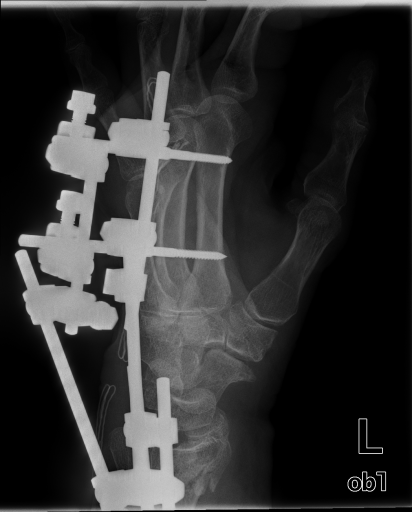

Image Dataset – The Image Retrieval in Medical Applications (IRMA) 2009 database is a collection of 14,410 x-ray images that have been randomly collected from daily routine work at the Department of Diagnostic Radiology of the RWTH Aachen University (Fig. 2). The downscaled images were collected from different ages, genders, view positions, and pathologies [33]. Each image in the dataset has an IRMA code. According to these codes, 193 classes are defined according to 2008 IRMA codes. The IRMA code comprises four axes with three to four positions each: 1) the technical code (T) (modality), 2) the directional code (D) (body orientations), 3) the anatomical code (A) (body region), and 4) the biological code (B) (the biological system examined). The complete IRMA code consists of 13 characters TTTT-DDD-AAA-BBB, with each character in . As many as 12,677 images are separated for training. The remaining 1,733 images are used as test data. In this project, the IRMA 2009 dataset has been used with specified 2008 IRMA labels (consisting of 193 classes) for retrieval purposes. Otherwise, same dataset is utilized with general 2005 IRMA labels (consisting of 57 classes) for classification purpose. 2005 IRMA labels are more general than 2008 IRMA labels because it has been made of 6 characters from top of hierarchical classes, TT-D-AA-B. In 2009 dataset, each image can not have been coded according to 2005 IRMA coding regularity. A total number of 12,631 images from training set and 1,639 images from testing set have 2005 IRMA codes. For this reason, SVM classification is implemented on corresponding images.